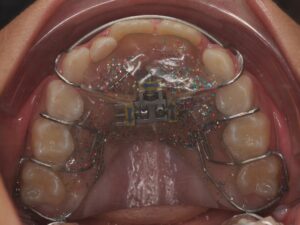

Il s’agit de l’orthodontie du jeune enfant. Elle permet d’intercepter un défaut de croissance ou d’éruption dentaire qui pourrait devenir irréversible s’il est pris en charge trop tard. De manière générale, il y a trois axes.

Il correspond à la réorientation des croissances des mâchoires supérieures et inférieures. En effet, tant que l’enfant est encore jeune, la croissance peut être déverrouillées, voire guidée afin qu’une croissance harmonieuse des mâchoires se fasse.

Il s’agit de la mastication, la respiration, la posture linguale, les habitudes déformantes. Elles font partie intégrante de la bonne posture des mâchoires et des dents. Elles seront également contrôlées et interceptées. Les appareils sont nombreux en fonction de la malocclusion, ils peuvent être fixes ou amovibles. Très souvent, l’interception pourra être associée à un rendez-vous chez : l'ORL, l'orthophoniste, le kinésithérapeute ou encore l'osthéopathe.